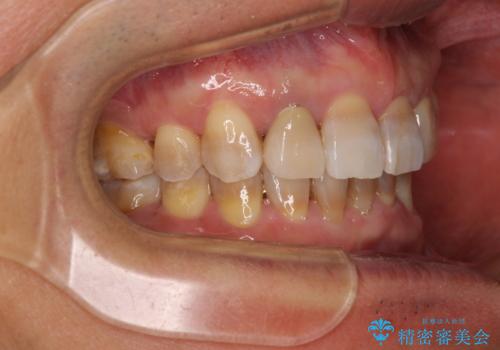

左右に骨格がずれて咬みにくい ワイヤー装置による抜歯矯正

- 骨格的な咬み合わせのズレ、前歯のデコボコとクロスバイトを気にして来院された患者様です。

全額的にデコボコが強いため、上下左右の小臼歯計4歯を抜歯し、ワイヤー装置による矯正治療を行うこととしました。

抜歯する歯の一部をセオリーである第一小臼歯ではなく、第二小臼歯にすることで、骨格的なずれをカバーするように計画しました。

小臼歯の抜歯する部位を選択したことで、安定した咬み合わせとなりましたが、第二小臼歯を抜歯した部分はスペースを閉じるのに長い期間を要しました。

矮小歯であった上顎前歯2本は、矯正治療後にバランスの取れた大きさのオールセラミッククラウンを装着しました。